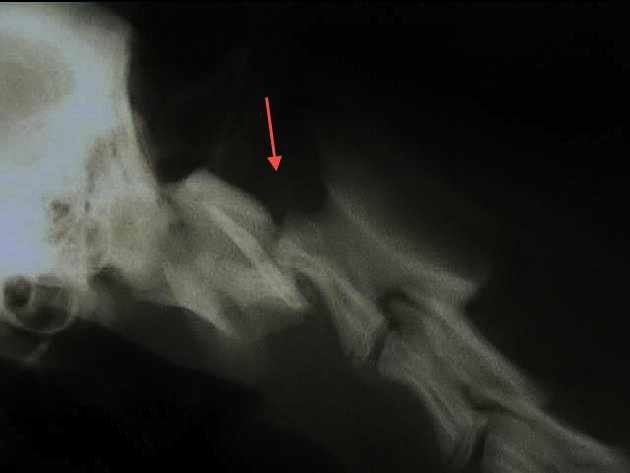

Radiographie de la colonne vertébrale:

En cas de difficultés locomotrices, il est possible de repérer des lésions des vertébrales. sur une radio sans préparation. L’injection de produit de contraste dans la colonne vertébrale (myélographie) est parfois nécessaire pour visualiser d’éventuelles compressions de la moelle épinière (hernies discales) qui peuvent être responsables de paralysies chez votre animal.